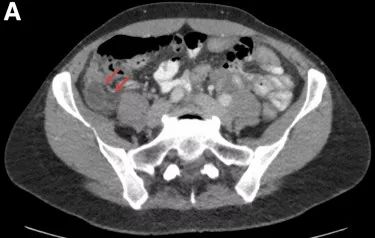

实验室检查发现白细胞计数升高,WBC 7.0 K/μL(参考范围4.5-11.0 K/μL)。腹部CT检查(图A)。

(图A 腹部CT检查)

腹部CT检查发现阑尾增大且周围存在微量液体(图A),与急性阑尾炎表现一致。患者经阑尾切除术后症状缓解并经病理检查确诊(图B)。